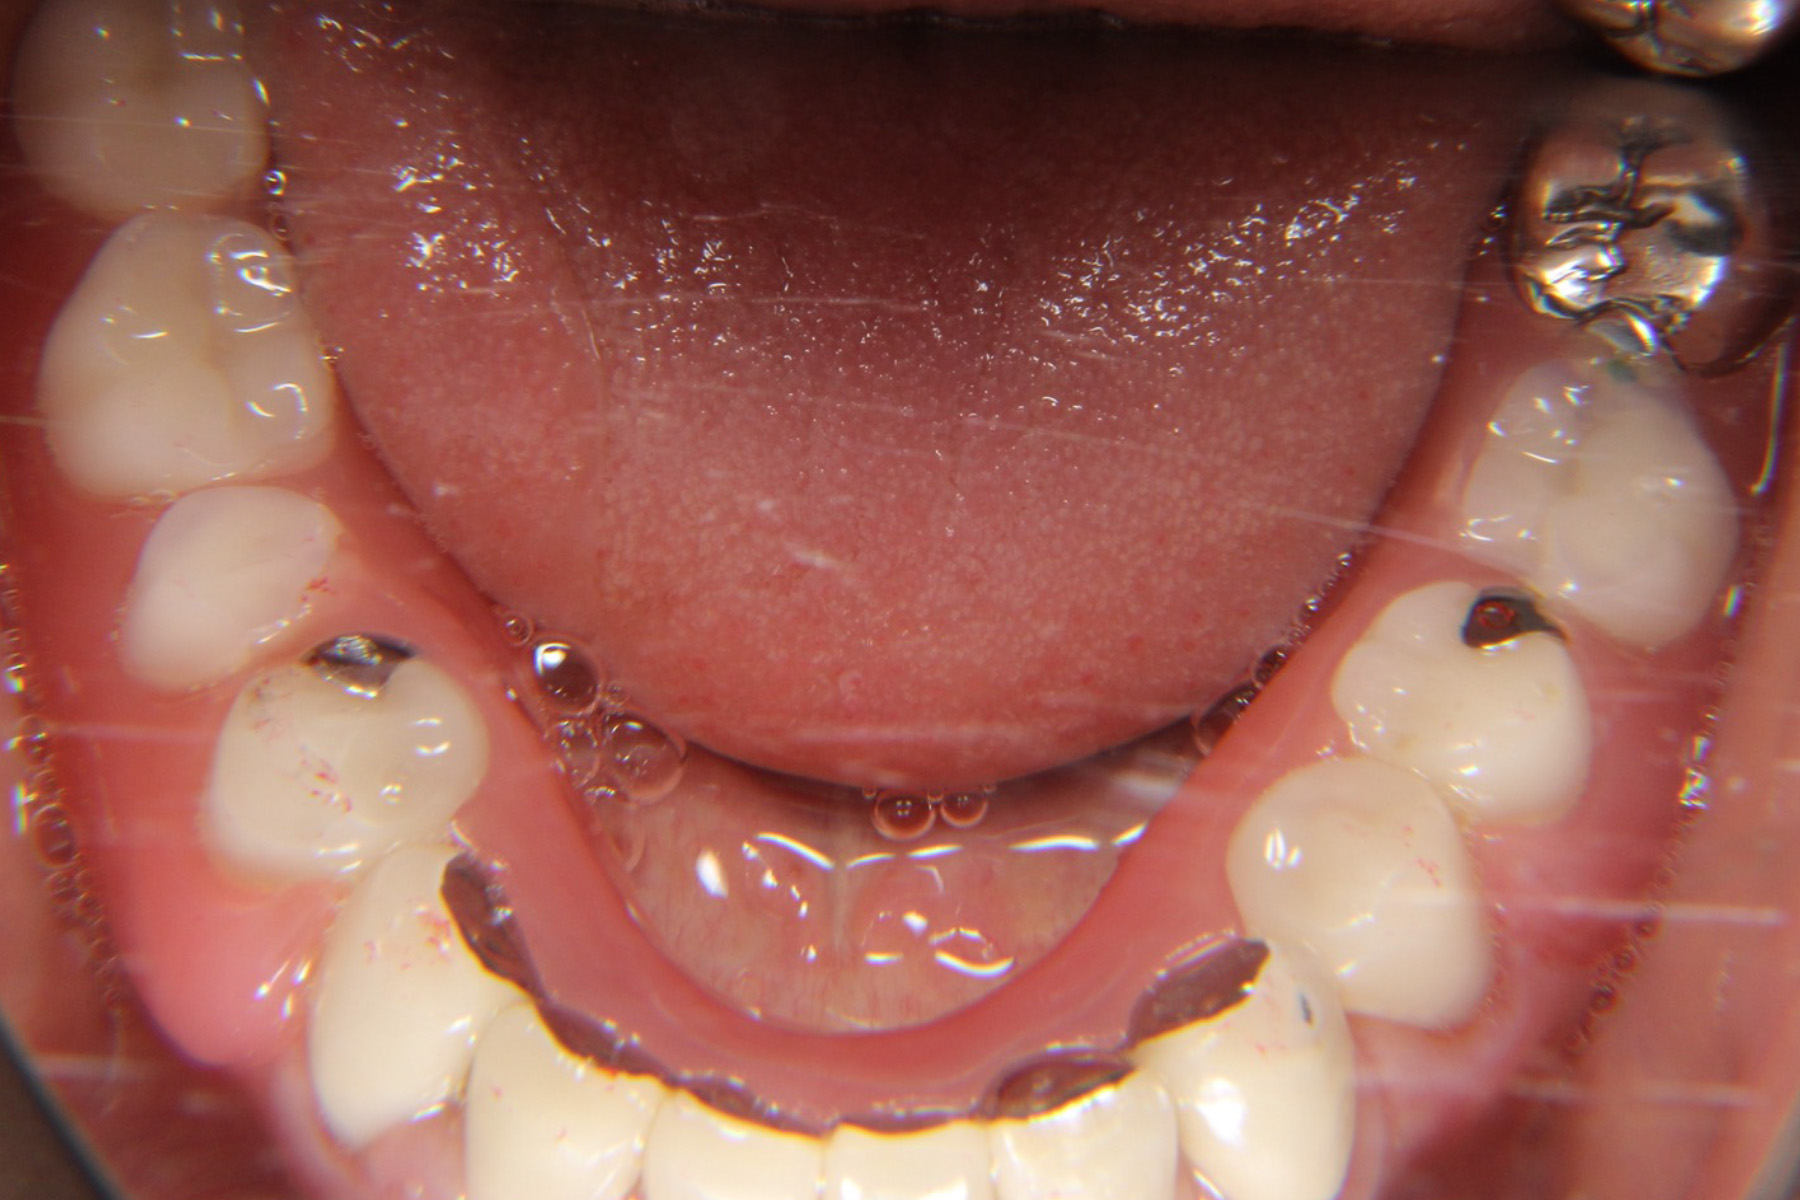

全顎的な治療を勧めたが、ご自身は義歯での治療を望まれたため患歯のみ抜去、保険内の義歯作成を行いました。

その後、やはり義歯での食事に限界を感じたためインプラント治療及び全顎的な処置をご希望。欠損の補綴及び全顎的な咬合回復・根尖性歯周炎の治療を行うこととしました。

| 治療内容 | 下顎の欠損部はインプラントにて対応。全3本を予定した上顎の欠損部はインプラントスペースがなかったためブリッジにて補綴。 失活歯の再根治を実施した上で全顎的なプロビジョナルを作成。咬合安定を図った上で最終補綴を行っていくこととしました。 |